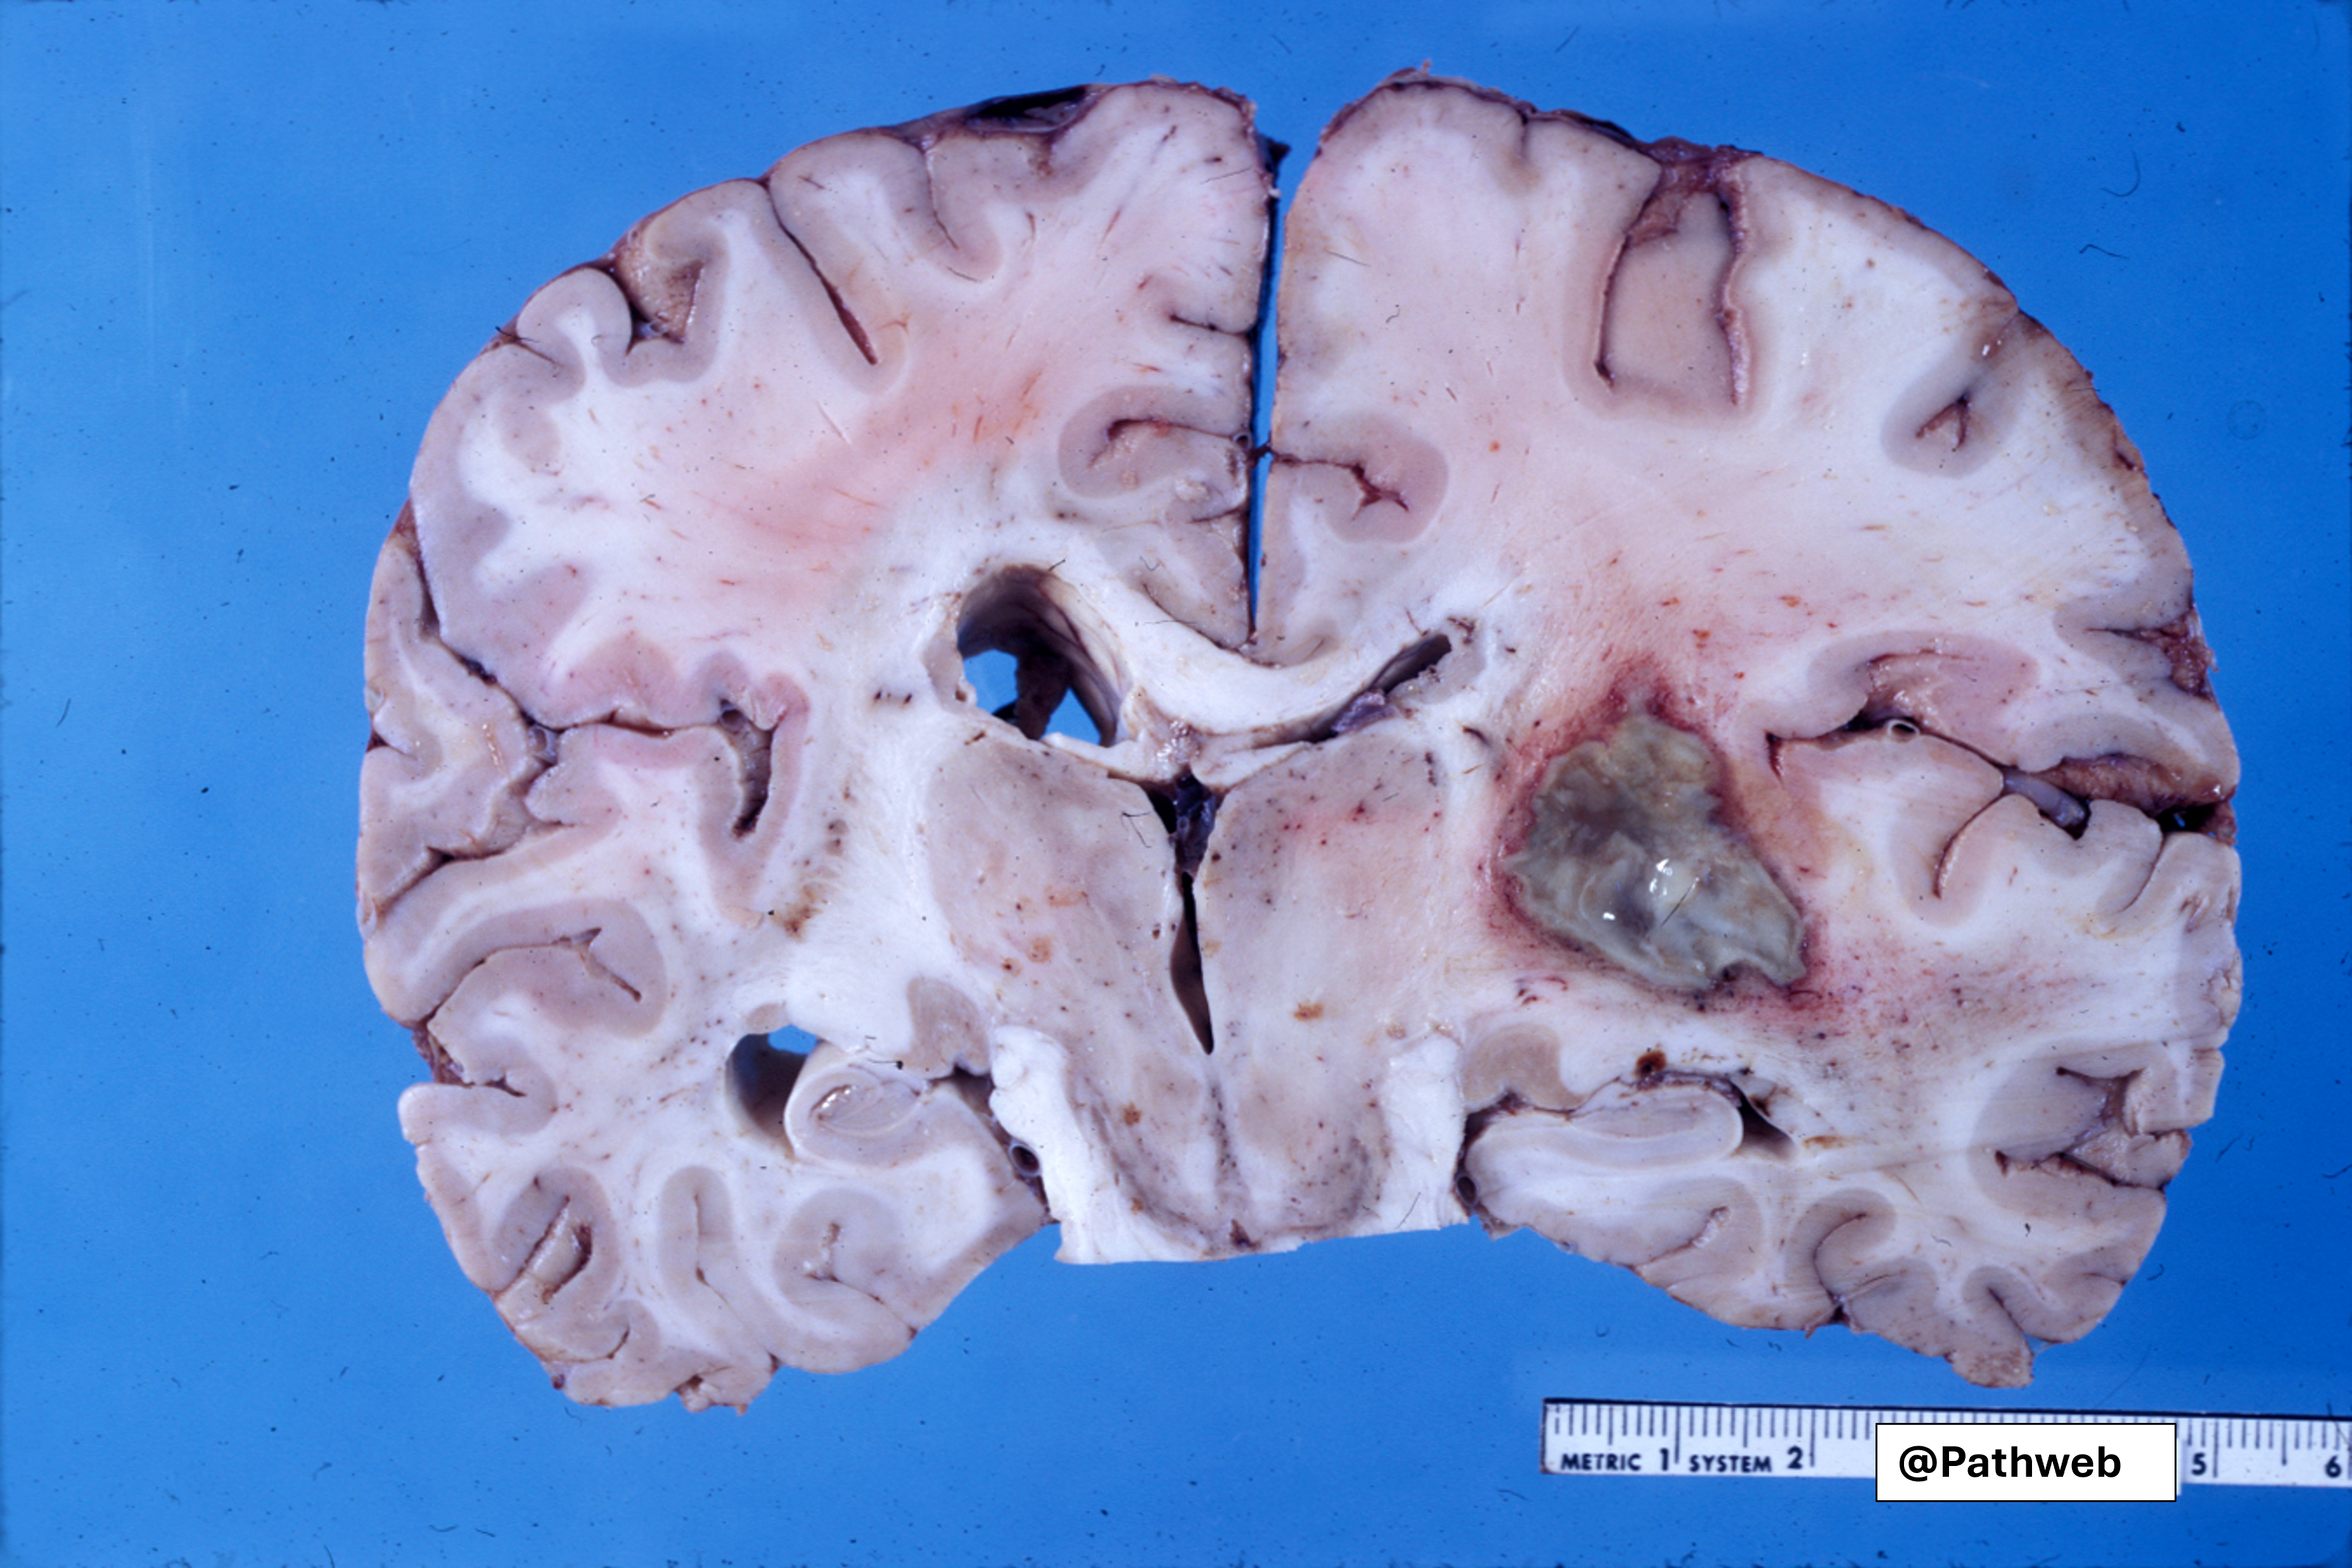

45 year old man with focal neurologic deficits, headache and fever for several weeks.

Cerebrospinal fluid (CSF) analysis showed increase in white cell count, elevated protein concentration but normal glucose content.

The affected cerebral hemisphere is swollen. Cut surface shows a large well-defined cavity (due to liquefactive necrosis and suppuration) lined by a layer of creamy fibrinopurulent exudate resting on a collagenous capsule.

There is compression but no rupture into the lateral ventricle.